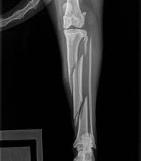

Kirschner副子(外固定)、髄内釘、ワイヤー、骨ネジ、骨プレート(内固定)などによる固定法が適用されます。

犬では腸骨外側面から接近して、中殿筋と深殿筋を背方へ反転し、骨プレートをネジで止めて骨片を固定します。大型犬では2本の海綿質用ネジで止めることもあります。

また多発骨折には、骨プレートと圧着ネジを併用します。Kirschner副子も使われます。

猫では、背側から腸骨に接近し、ワイヤーによる縫合に、Kirschnerワイヤーの挿入を併用します。

犬では後外側面から接近し、髄内釘、ワイヤーまたは骨プレート(2孔)によって固定します。腸骨体の骨折が合併している時には、腸骨体の手術を先に行う。

坐骨結節の骨折には、2本の圧着ネジを挿入して固定する。

猫では、直腸に指を挿入して骨片の整復をはかり、Kirschnerワイヤーで固定します。

ワイヤー、骨プレートで固定するか、圧着ネジまたは髄内釘を使用する。